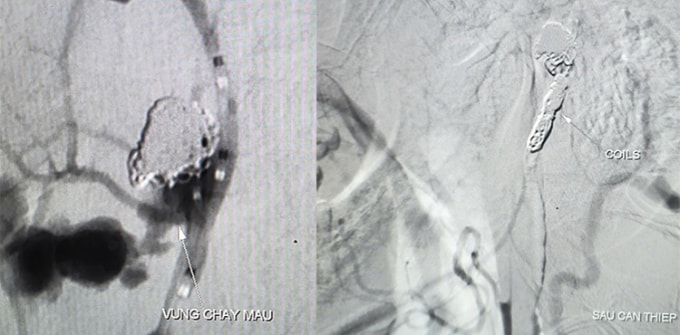

Kết quả CT Scan ghi nhận tổn thương vùng dạng khối choán chỗ khoang niêm mạc hầu của bệnh nhân, xâm lấn vào động mạch cảnh trong, ổ giả phình động mạch cảnh trong đoạn dưới nền sọ. Bác sĩ Trần Công Khánh, Phó Trưởng khoa Chẩn đoán hình ảnh cùng ê kíp chụp và can thiệp cầm máu dưới mạch số hóa xóa nền (DSA) cho bệnh nhân, ghi nhận ổ giả phình động mạch cảnh ở cổ kích thước 4,2 x 4,8 mm, cổ túi phình rộng đang chảy máu.

Êkíp dùng bóng chẹn dòng chảy kiểm soát lượng máu chảy ra, luồn ống thông siêu nhỏ đến vị trí túi phình thả 9 vòng xoắn kim loại (coils) để làm tắc hoàn toàn ổ giả phình và động mạch cảnh, kiểm soát triệt để nguồn chảy máu. Quá trình can thiệp trong 90 phút, bệnh nhân được truyền 6 đơn vị máu, hiện không yếu liệt chi, sức khỏe phục hồi.